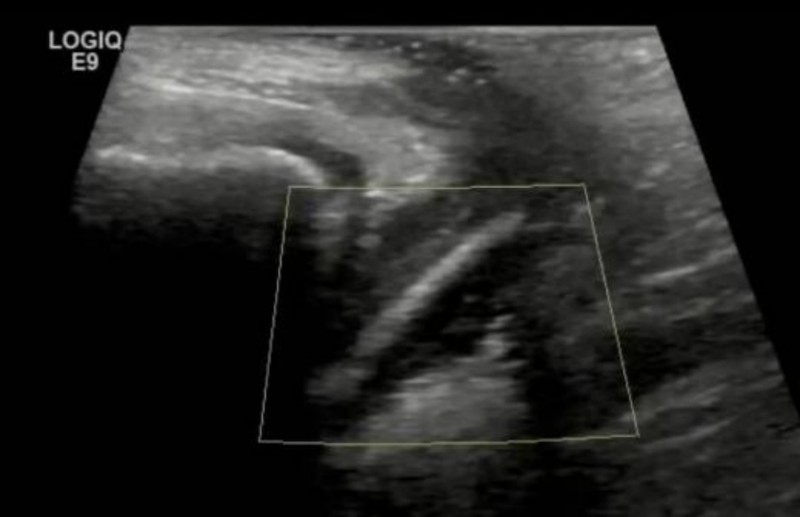

传统妇科检查对儿童阴道异物检出率极低。超声虽能发现部分病例,但敏感度受限于异物材质与位置。阴道内镜技术的出现,彻底改变了这一困境。